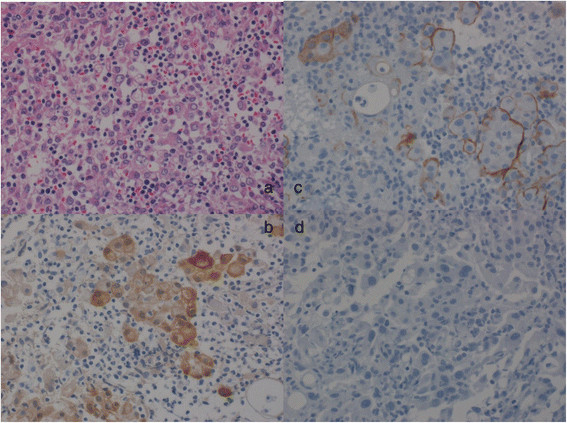

Two weeks after OK-432 infusion, EPP plus mediastinal lymph node dissection, combined with chest wall resection, including the first two ribs, the pericardium, and the diaphragm, was performed via a sigmoid incision of the fifth intercostal space. The pericardium and the diaphragm were reconstructed using polytetrafluoroethylene Blood loss and the duration of surgery were 1085 g and 490 minutes, respectively. Histological analysis showed that, the mesothelioma cells reached the fascia of the major pectoral muscle invading the intercostal muscles and partially destroying the ribs. However, pathological investigation confirmed that all the surgical margins were tumor-free. In addition, microscopic findings showed the aggregation of inflammatory cells, lymphocytes, plasma cells, and histiocytes with the mesothelioma cells (Figure 2). Postoperative immunohistochemical analysis confirmed the diagnosis of epithelioid-type MPM. Mesothelioma cells stained positive for calretinin, D2-40, CAM5.2, vimentin, and myoglobin, but were negative for PE-10, TTF-1, and CEA. The Ki67 and p53 labeling indices of the mesothelioma cells were 30–40% and 10%, respectively.

Figure 2.

Histopathological and immunohistochemical examination of the resected tumor revealed epithelioid-type malignant pleural mesothelioma. a. Hematoxylin and eosin staining at the site of chest invasion shows malignant pleural mesothelioma and inflammatory cells. b. Calretinin positivity. c. D2-40 positivity. d. Thyroid transcription factor-1 negativity.